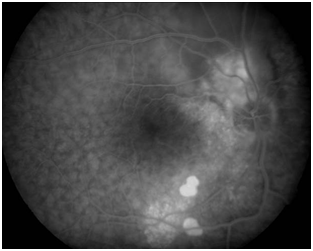

Central serous chorioretinopathy (CSC) is a chorioretinal disorder characterized by serous detachment of the neurosensory retina. CSC occurs most frequently in mid-life and more often in men than in women. Major symptoms are blurred vision, usually in one eye only and perceived typically by the patient as a dark spot in the centre of the visual field with associated micropsia and metamorphopsia. Normal vision often recurs spontaneously within a few months. The condition can be precipitated by stress and hypercortisolism. Ophthalmoscopic signs of CSC range from mono- or paucifocal RPE lesions with prominent elevation of the neurosensory retina by clear fluid – typical of cases of recent onset – to shallow detachments overlying large patches of irregularly depigmented RPE. The spectrum of lesions includes RPE detachments. Granular or fibrinous material may accumulate in the subretinal cavity. Serous detachment often resolves spontaneously (Figure 1B).

Figure 1B OCT shows neurosensory detachment of the macula.